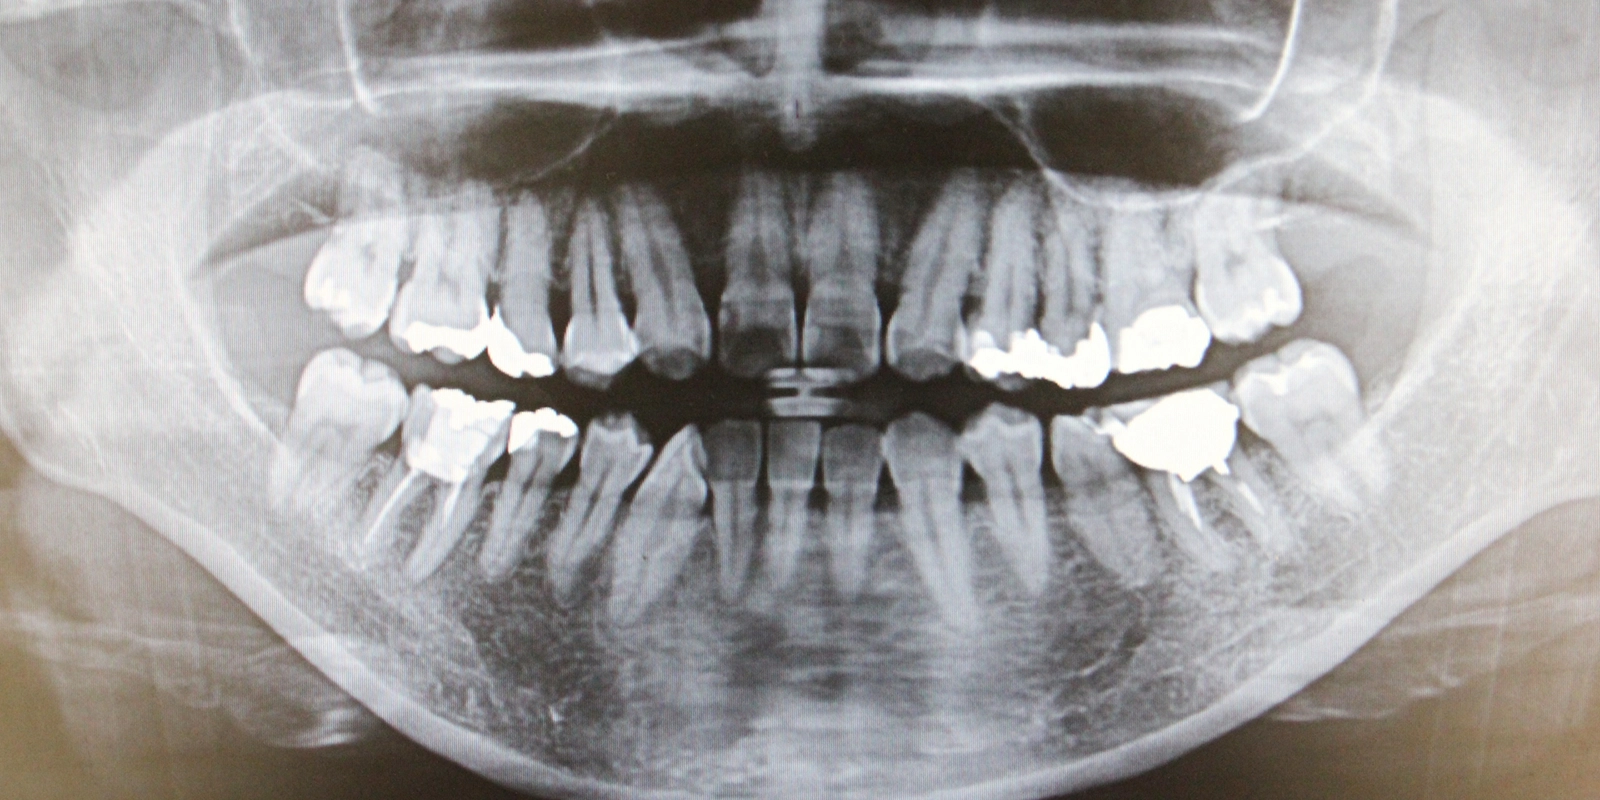

「パノラマレントゲン」は、上下の歯全体と顎の骨を一枚の画像で撮影する方法です。

全体的な状態を把握するには有用ですが、個々の歯の詳細を見るには解像度が十分ではありません。そのため、歯根破折の疑いがある場合は、パノラマレントゲンで全体像を把握した後、デンタルレントゲンで詳しく確認するという流れが一般的です。